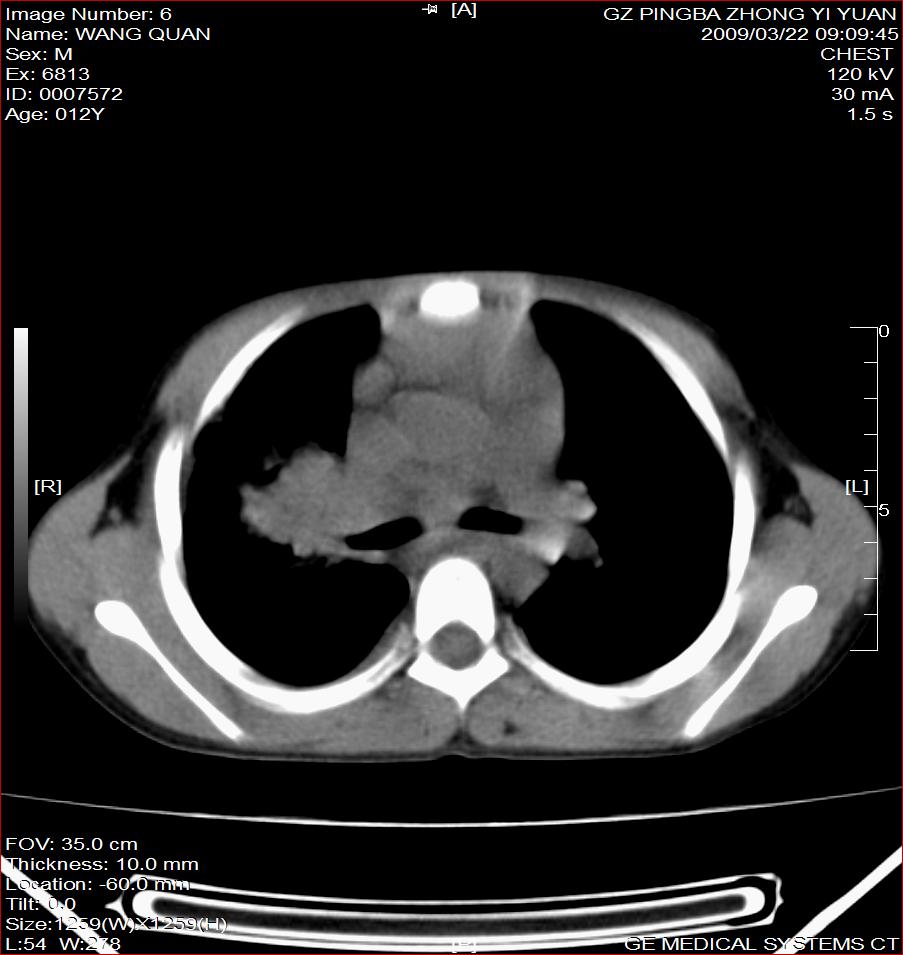

以下是引用随光逐影在2009-3-23 8:12:00的发言:[br]1)右肺门及纵隔淋巴结结核。2)两肺急性血行播散型肺结核可能。3)右侧支气管内膜结核?建议必要时行纤支镜检查。4)右侧少量胸腔积液。